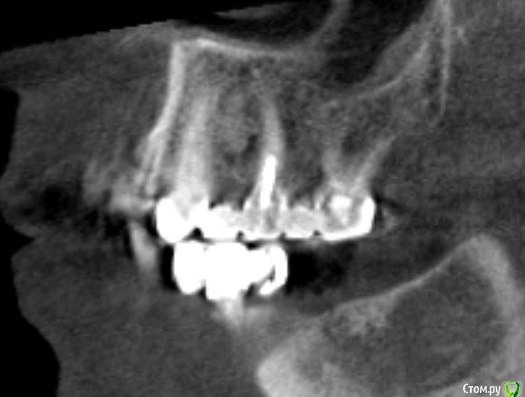

Мк стоят около 10 лет,в области 23 средней 1/3 определяется свищ,отделяемого нет,небольшое западение альвеолярного отростка с рубцовыми изменениями слизистой в области 24 ,перкуссия 23,25 безболезненна,болезненность в области переходной складки и небной поверхности на уровне апекса 23

Со слов пациента периодически возникающий отек,тянущие боли

Около недели назад был похожий случай: пациент мост 1.6-1.4. В промежутке неясного генеза убыль кости по снимку. Делаем КТ - очаг просветления в области отсутсвующего зуба, по снимку  вроде кость 4 типа. Объясняю пациенту, что будем ставить имплантат, раскроемся и увидим что там. День Х, после отслоения в области удаленного зуба 1.5 грануляционная ткань! 30 минут кюретажа всех этих спаек и получена практически первоначальная лунка удаленного зуба 1.5. Закинул кость и вкрутил имплантат. Ушил, а на момент когда пациент вышел из кресла - сказал, что сало прям легче. мол было даже желание вам доктор помочь все это из лунки убрать))) 2 недели все гуд - ничего не беспокоит. Так вот к чему так много букав: скорее всего удалили зуб и не сделали кюретаж, там грануляционная ткань которая дает всю эту картину. Побольше бы срезов с КТ. И сделайте сагитальные срезы. Если полость из неоткуда то режьте и смотрите.

насчет 27 ниче не хочу говорить по этим снимкам